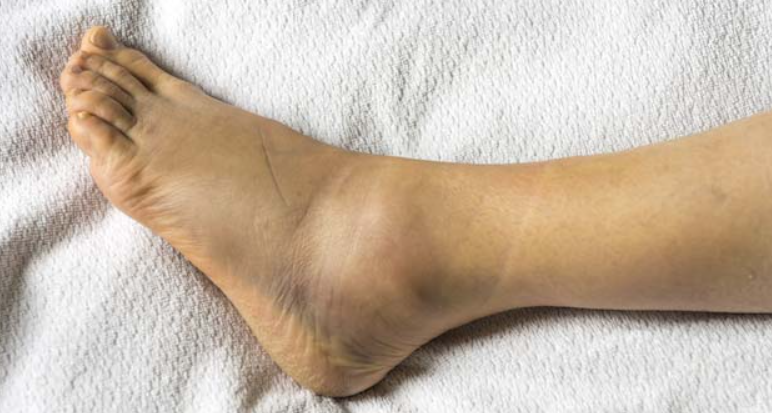

부종(붓기): 인대 주변이 붓거나 멍이 들 수 있음

♼ 손상 정도 구분

1도: 인대가 약간 늘어나거나 미세손상(염좌)

2도: 인대가 부분적으로 파열됨

3도: 인대가 완전히 끊어진 상태(완전 파열)